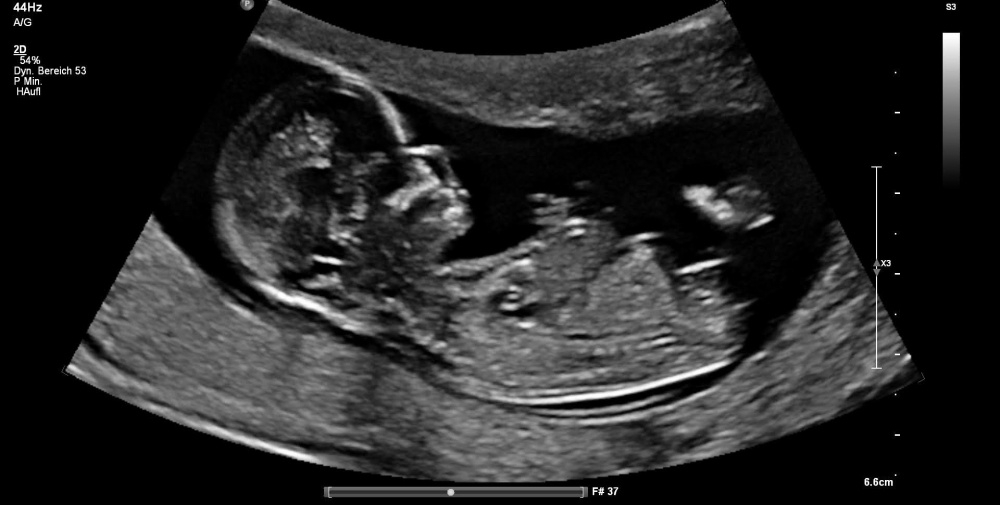

ich bin in der 28. Ssw und die Tendenz ändert sich laut FA ständig. Irgendwie verwirrt mich das völlig 🙈

In der 13.Ssw und 18.Ssw meinte er zu 90% ein Junge.

In der 23.Ssw konnte er gar nichts sagen.

In der 26.Ssw hieß es dann zu 90% Mädchen.

Dann musste ich in der 27. Ssw aufgrund von schmerzen nochmals hin und hier hieß es dann wieder, dass er sich nicht sicher sei...

Vielleicht könnt Ihr mir ja helfen :-)

Vielen Dank schonmal

Ich hänge mal ein Bild an.